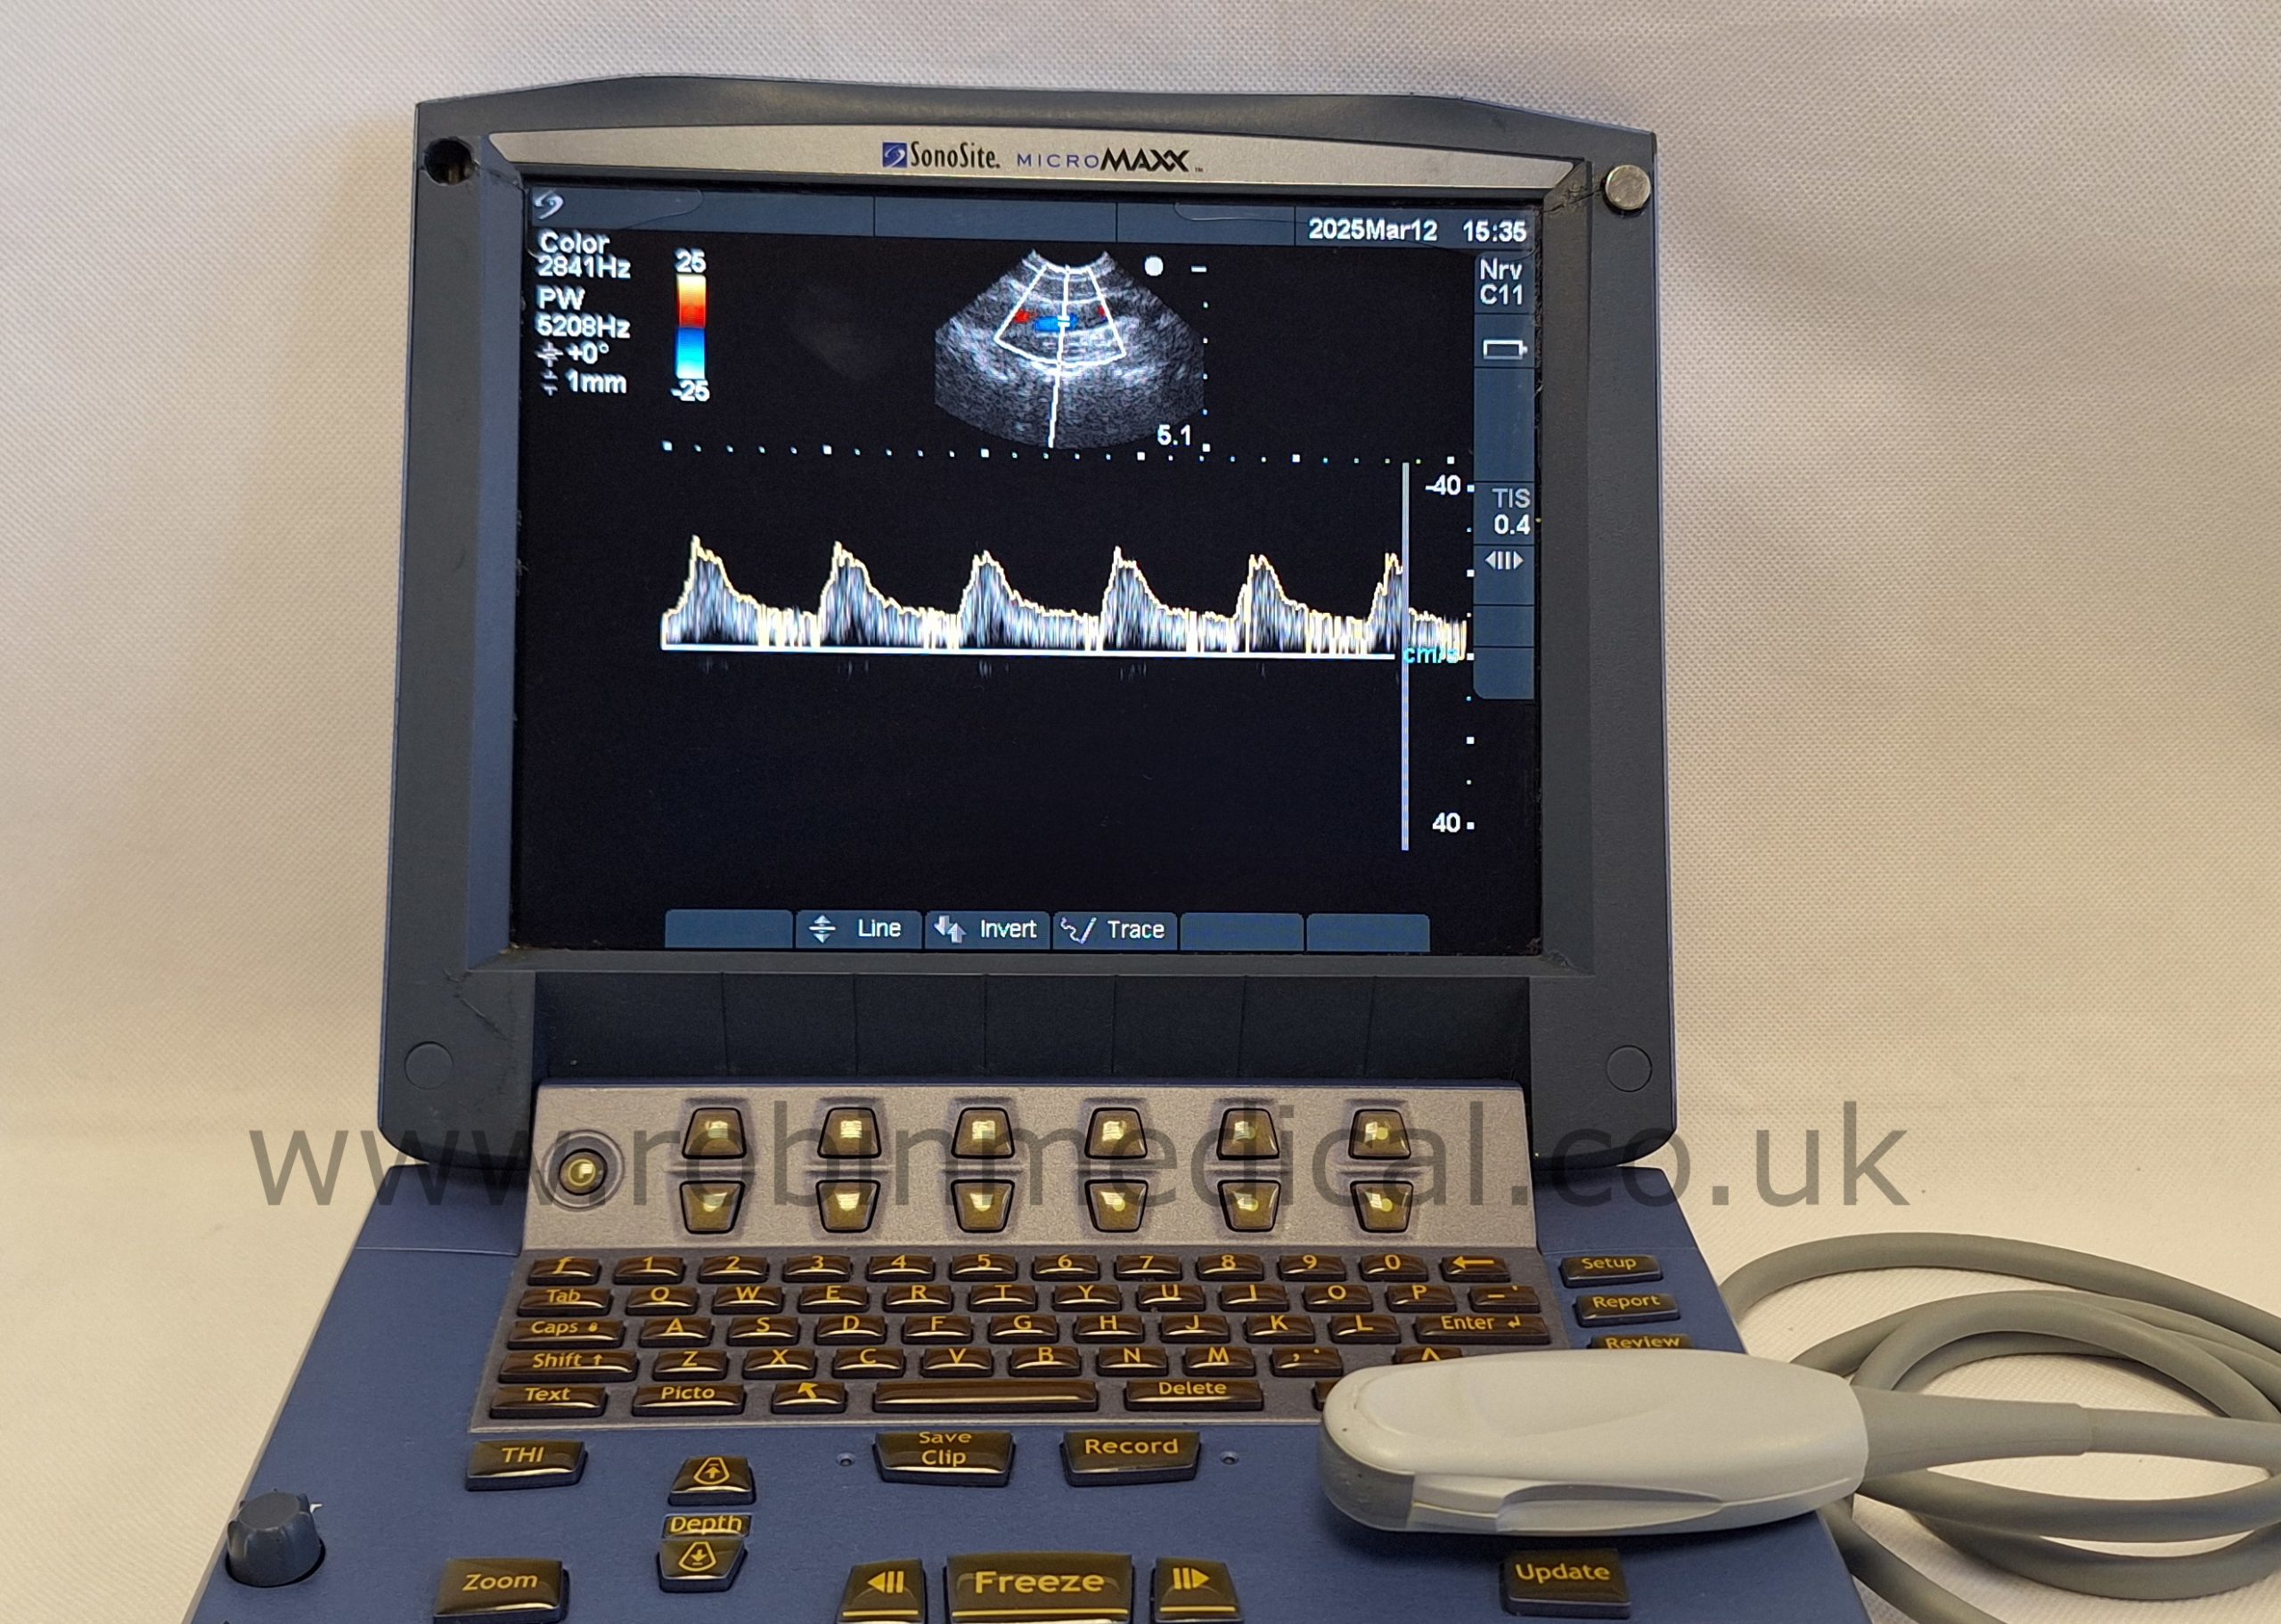

The Sonosite C11e P07161-16 is a high-performance curved-array transducer designed for the Sonosite MicroMaxx ultrasound system. With a frequency range of 8–5 MHz, it delivers exceptional imaging clarity for abdominal, pediatric, and vascular applications. Its compact 11 mm footprint makes it ideal for scanning in narrow or confined anatomical regions, while maintaining superb detail resolution. This probe offers versatility and portability in fast-paced clinical environments.

| Imaging Modes | 2D, M-Mode, Color Doppler |

The probe functions as intended and the condition is exactly as shown in images.